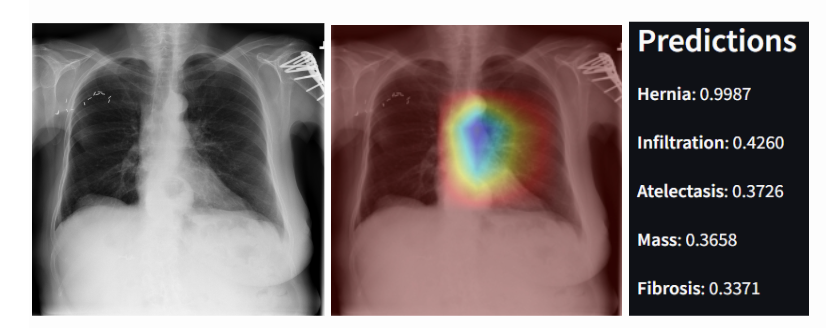

Figure 1: (Left) An example of an X-Ray from the NIH ChestX-ray14 with Hernia and Infiltration as its ground truth findings. (Center) Grad-CAM visualizations of the same X-Ray image. (Right) DannyNet’s predictions of the 5 most likely findings in the image.

This is an example of an X-Ray diagnosed with both a Hernia and Infiltration. The model correctly assigns the highest probability to the correct diseases (hernia and infiltration), but it only predicts that Hernia has a probability above 50%. This behavior reflects the model’s high sensitivity (as indicated by a high AUC) but lower precision, leading to a lower F1 score. The model is good at ranking the correct disease highest, but less effective at distinguishing between the presence and absence of each disease. This observation is consistent with the trade-off between sensitivity and specificity in imbalanced datasets.